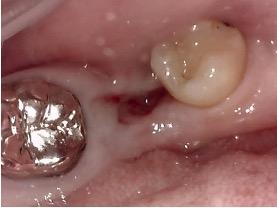

上の写真はなんと親知らずが、手前に移動しています。

下の一番奥歯がなくなって、親知らずを手前に移植しました。